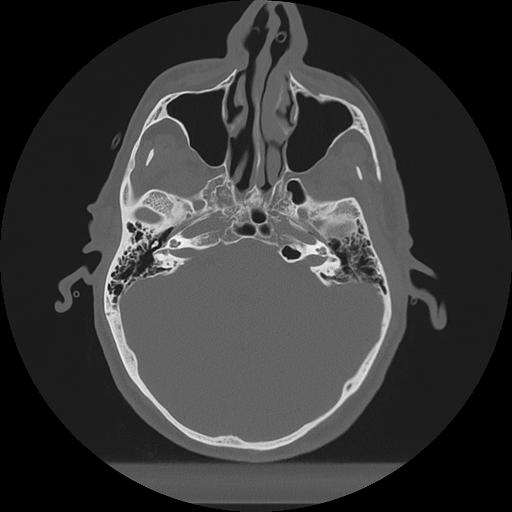

11 HUESO,,Axial,2.0,HUESO,,